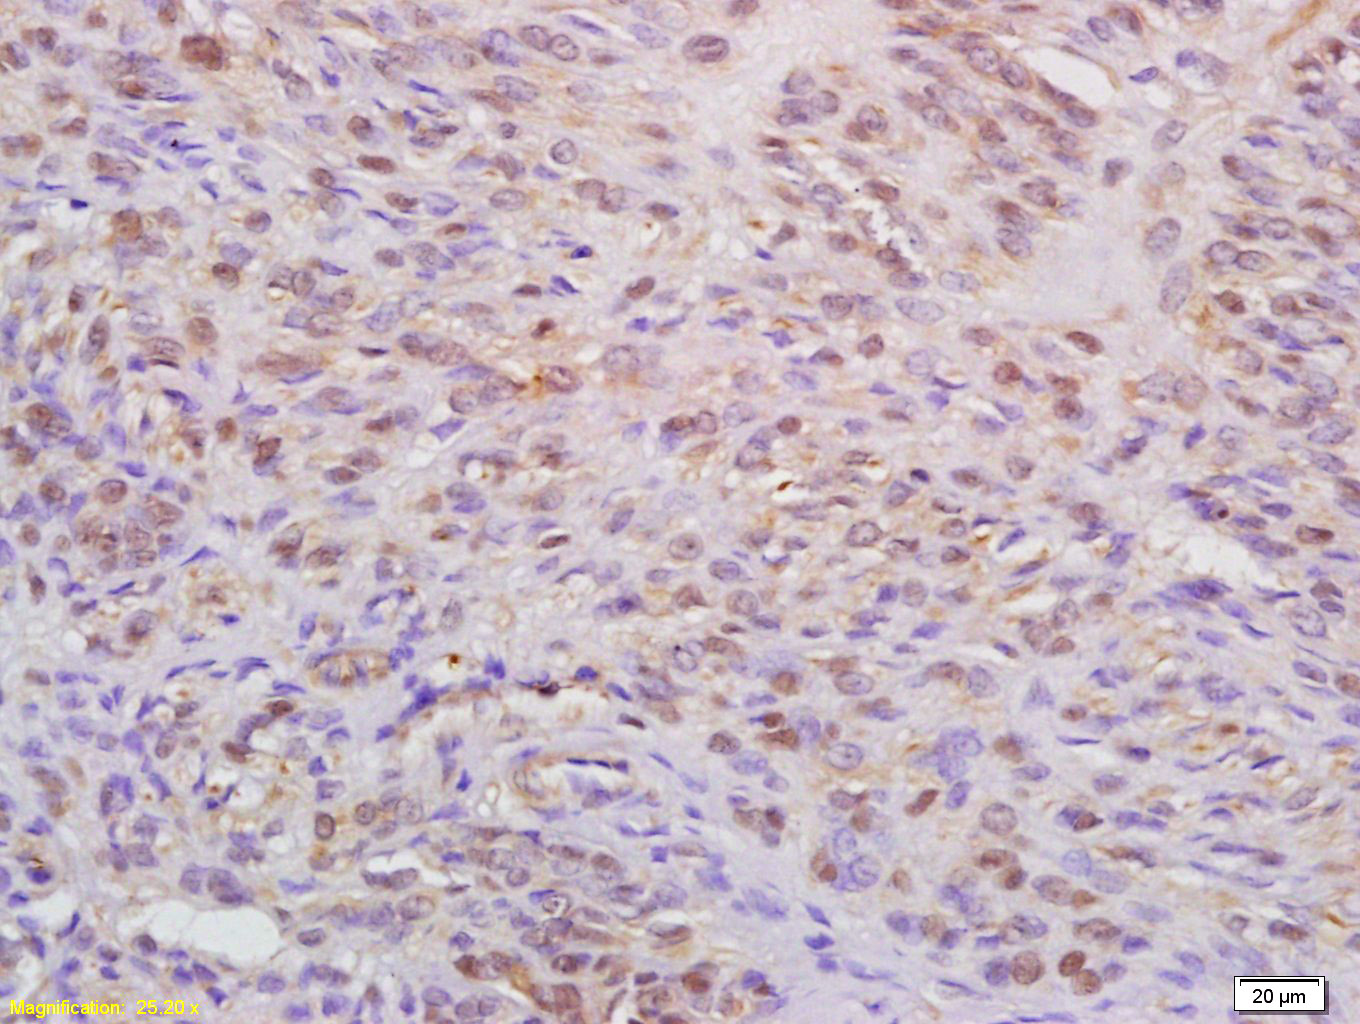

Tissue/cell: human cervical carcinoma; 4% Paraformaldehyde-fixed and paraffin-embedded; Antigen retrieval: citrate buffer ( 0.01M, pH 6.0 ), Boiling bathing for 15min; Block endogenous peroxidase by 3% Hydrogen peroxide for 30min; Blocking buffer (normal goat serum,C-0005) at 37℃ for 20 min; Incubation: Anti-WAPL Polyclonal Antibody, Unconjugated(bs-7733R) 1:200, overnight at 4°C, followed by conjugation to the secondary antibody(SP-0023) and DAB(C-0010) staining